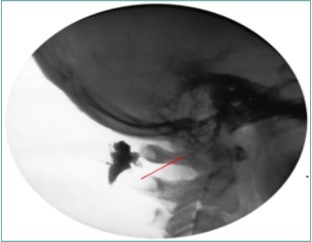

Figure 8.Lateral fluoroscopic image showing the needle in the suboccipital space; red shows the level of the spinous processes (red line). Image Courtesy of Gabor Racz, MD

Figure 9.Lateral Fluoroscopic image showing initial contrast location deep to the suboccipital muscles; red line corresponds to the level of the inferior oblique capitus muscle. (Image courtesy of Gabor Racz, MD)

Figure 10.Lateral fluoroscopic image showing the final contrast spread; the arrow shows the outline of the greater occipital nerve at the level of the inferior oblique capitus muscle. Image Courtesy of Gabor Racz, MD